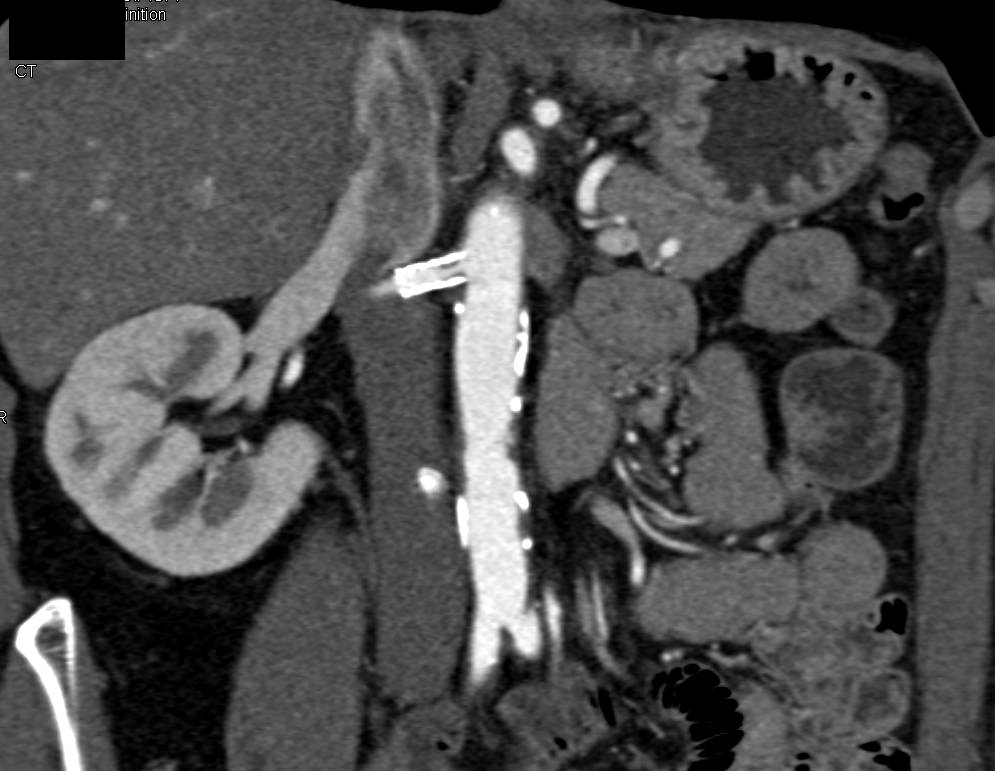

Transitional Cell Cancer (TCC) in Upper Pole of Right Kidney